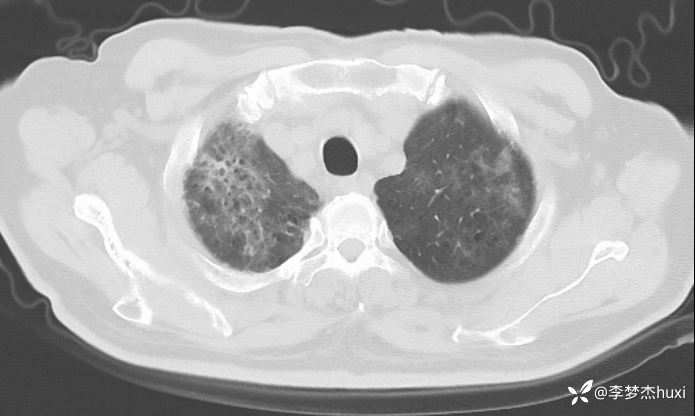

男性74岁,莫西沙星治疗加重的肺炎,可能什么病原菌?

既往史:既往高血压病史 20 余年,最高 180/90mmHg,平素口服降压零号治疗,控制可;糖尿病病史 20 余年,平素应用诺和灵 30R,控制良好;右肺鳞癌病史11月,放疗结束3天,期间放射性食管炎,目前仍吞咽痛;否认冠心病病史;否认“肝炎”、“结核”等传染病史;否认外伤史,否认手术史,无输血史,否认药物、食物过敏史;预防接种史不详,系统回顾无特殊。。

治疗经过:莫西沙星、喜炎平治疗进展

讨论:可能什么病原体?